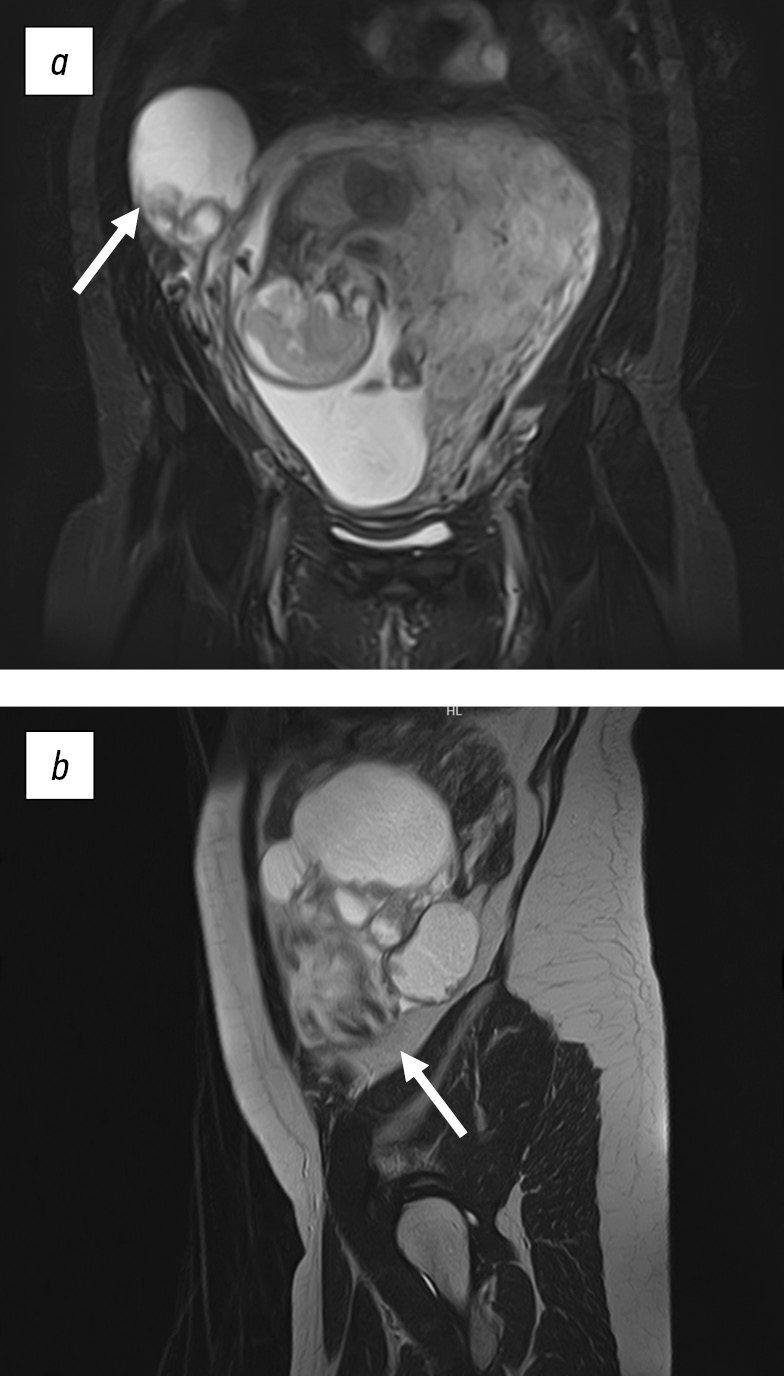

According to dopplerometry results at a gestational age of 33 2/7 weeks, an increase in circulatory disorders in the mother–placenta–fetus system from degree IA to degree II was recorded. A repeated MRI study of the pelvic organs was performed, which revealed partial regression of the tumor (Fig. 3).

Fig. 3. Magnetic resonance tomograms, weighted by T2, in the axial (a) and coronal (b) planes, showed a solid neoplasm of the left ovary, 19 × 14 × 12 mm in size

The case conference had discussion regarding the patient in order to determine further therapeutic approach. Taking into account the presence of fetal growth retardation syndrome and incident disorders of fetal-uterine blood flow, it was decided to refuse PCT cycle 3 due to the high risk of perinatal complications. In addition, performing preterm delivery by cesarean section with a single-step surgery in a radical volume (extirpation of the uterus and left appendages, omentectomy) and subsequent continuation of PCT was decided. In the early postpartum period, suppression of lactation is indicated due to the need to continue PCT, which is incompatible with breastfeeding.